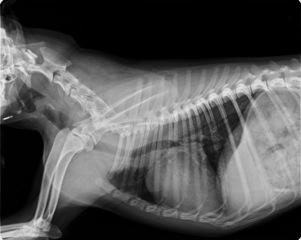

LA TRACHEA è un organo dell’apparato respiratorio, la cui funzione primaria è trasferire l’aria dall’esterno ai polmoni, ripulendola e umidificandola. Possiamo immaginarla in fiamme, la trachea , come una sorta di lungo tubo che comincia nella parte inferiore della gola, attraversa tutto il collo e termina all’interno della cassa toracica. Tracheite nel cane , ecco i sintomi e come curarla. La laringite è una infezione o infiammazione della laringe (tessuto e cartilagine che ostruisca la parte superiore della trachea durante la deglutizione per impedire soffocamento). Se la tracheite è dovuta da un virus, verranno somministrati degli antibiotici per via orale e degli antiparassitari mentre, se si tratta di un corpo estraneo, si tende a lasciare che il cane lo espella con le feci.

Avevamo parlato tempo fa di quanto siano da non sottovalutare le malattie respiratorie nel cane : tra queste oggi prendiamo in considerazione la tracheite. La tracheite nel cane è un’infiammazione della trachea che può avere cause di varia natura. I sintomi della tracheite nei cani I sintomi possono variare a seconda della gravità o della sua origine.